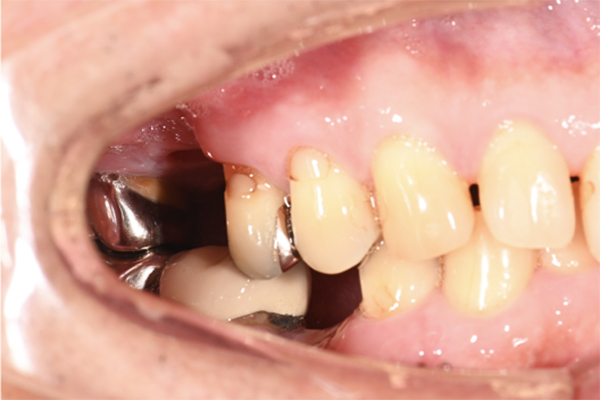

| 主訴 | 右下の奥歯が痛い |

|---|---|

| 治療内容 | 右下奥歯が割れていたため抜歯、その後インプラント治療を行った。(左の写真は抜歯後の写真) |

| 治療期間 | 4ヶ月 |

| 治療費 | 41万5千円 |

| 治療 リスク | 抜歯後インプラントの処置まで3ヶ月程度治癒期間(骨ができるまでの期間)が必要なことがあります。 |